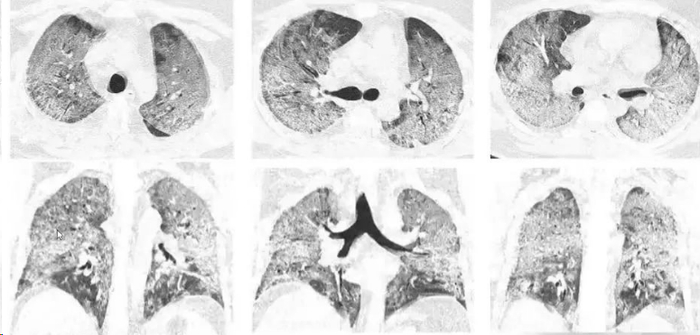

转自:医学界网站

近期,“女子硬抗流感10天两个肺都变白了”的热搜引发关注!据悉是来自江苏51岁的陈女士,近日感染流感,可她未前往医院就诊,而是在家硬扛10余天。感觉身体明显不适后才前往社区医院就诊,在输液时突发晕厥。经CT检查因肺部感染多种病毒,陈女士已经发展成重症肺炎,肺功能基本丧失,严重呼吸衰竭,随时有生命危险!

接诊医生表示:“患者两个肺都是白的,患有甲流合并多种细菌混合感染。”经过10多天治疗终于好转。因其患有糖尿病多年,免疫力偏低,患流感后“硬抗”大大增加了致病菌的感染风险,最终导致“白肺”!

“白肺”并不是一个专业的医学术语,是肺部影像学表现的一个口语化描述,因而并没有一个严格的医学定义。临床上,“白肺”一般指肺部大面积炎症所产生的影像学表现,具体表现为双肺浸润影,多见于急性呼吸窘迫综合征(ARDS)。